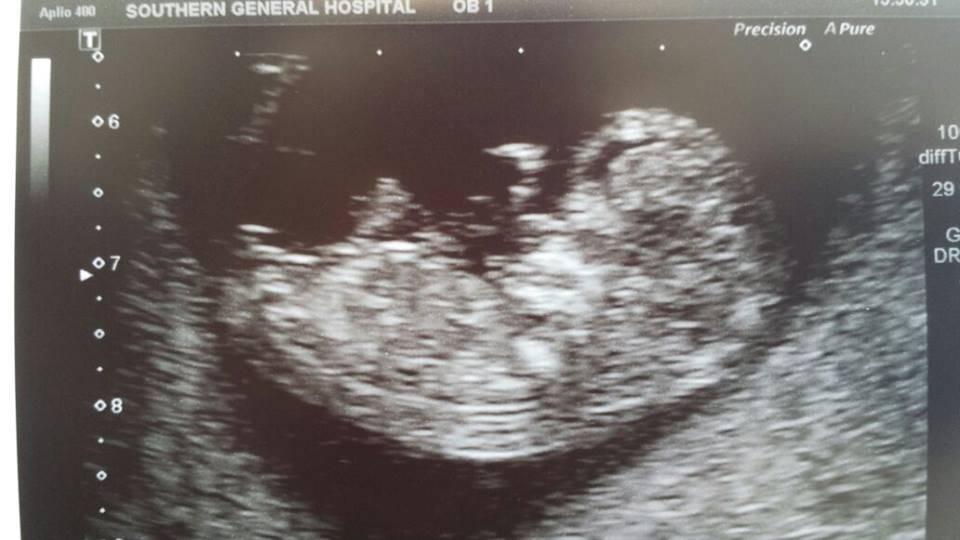

I am slowly starting to regret not finding out the gender of our baby at my last ultrasound scan and now it's driving me up the wall waiting....and waiting!

I would really appreciate any guesses as to whether my baby is a boy or a girl!